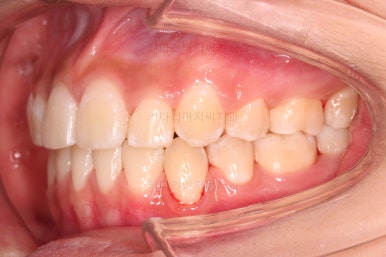

치료 종료시의 모습이에요.

총 21개월 걸렸고요.

발치를 중간에 결정했기 때문에 조금 지체된 면이 없지 않았으나 기간부터 치료 결과까지 만족스러운 치료였습니다.

동래교정치과의 전후 사진을 비교해 볼게요.

치여링 가지런해졌고, 교합과 중앙선 등 입안의 모습이 매우 좋아졌어요.

입매도 본인이 원하는 정도로 만들었고, 웃는 모습, 뻐드러졌던 각도도 매우 잘 개선이 되었네요.

기울어보이던 치열의 경사도 개선이 되었고요.